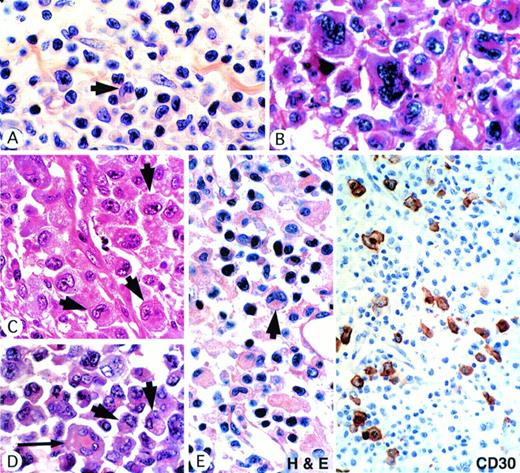

It was evident from the morphologic review that the ALK-positive tumors showed a broad spectrum of features, ranging from small-cell neoplasms that many pathologists might have categorized as pleomorphic T-cell lymphomas (Fig 1A) to cases at the opposite extreme in which very large cells predominated (Fig 1B). However, all cases shared one common feature, notably the presence of a population of large cells with a highly characteristic morphology (Fig1A through E). The nucleus lay eccentrically within these cells and was horseshoe or kidney shaped. In most cases, some crown-like nuclei could also be seen (Fig 1D). Nucleoli were less prominent than in Reed-Sternberg cells and often an eosinophilic region was seen near the nucleus, probably representing a prominent Golgi apparatus (Fig 1A through E).

ALK-positive ALCLs show a wide morphologic spectrum. (A) Small-cell pattern. A predominant population of small cells with irregular nuclei is associated with scattered large hallmark cells (arrow) showing eccentric lobated nuclei. (B) Giant-cell–rich pattern, showing striking cellular pleomorphism. (C) Common-type ALCL showing several hallmark cells (arrows). (D) Common-type ALCL showing several hallmark cells (arrow) and also a cell with crown-like nuclei (long arrow). (E) Lymphohistiocytic variant showing, in the hematoxylin and eosin-stained section, a single hallmark cell (arrow). Note the eosinophilic paranuclear area. Other cells are nonneoplastic, including histiocytes and plasma cells. Immunostaining of this case for CD30 highlights the scattered malignant cell population.

Once the characteristic features of these hallmark cells had been recognized, it was easy to identify them in all cases in the series, whatever the overall morphologic appearance (Fig 1A through E). In cases showing lymphohistiocytic features, these cells were less easily identified because of the large numbers of reactive histiocytes, but were nevertheless present (Fig 1E). In small-cell variant cases, these characteristic cells were mainly found around vessels in a perivascular pattern best seen in immunostained sections (see below).

The results of the present study of ALCL expressing ALK protein provide strong evidence that the morphologic patterns described in previous reports as representing possible subtypes of ALCL, eg, common type, lymphohistiocytic, or small-cell patterns,19,20,22 33 are morphologic variants of the same disease entity. All of these morphologic patterns could be found within this series, and in some instances different subtypes coexisted in a single biopsy or were found in successive biopsies from a single patient (Table 3). The link between these morphologic subtypes of ALCL was further reinforced by the presence in all cases of a highly characteristic large cell that can be considered as a major distinguishing hallmark of the disease (Fig 1). One of its distinguishing features is a perinuclear eosinophilic region that we assume represents a prominent Golgi apparatus. We have not shown this directly (by electron microscopy), but it is noteworthy that CD30 staining frequently highlights the same area (Fig 5A).